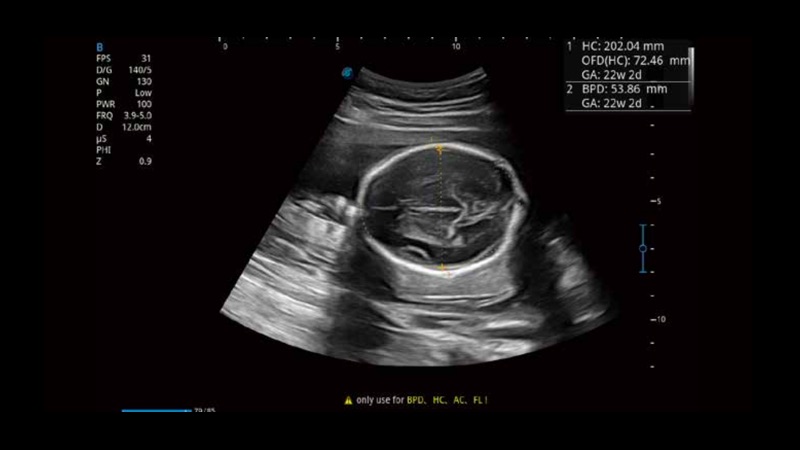

S-Fetus基于大數據深度學習算法,能夠幫助您在產前篩查過程中智能識別胎兒標準切面、自動測量并錄入報告。一個按鍵,即可智能、精準、高效地獲取胎兒生理指標,極大簡化您的產科檢查操作。

可快速對產科掃查切面完成胎兒生理學參數的自動測量,減少操作者按鍵次數,大幅提升檢查效率。